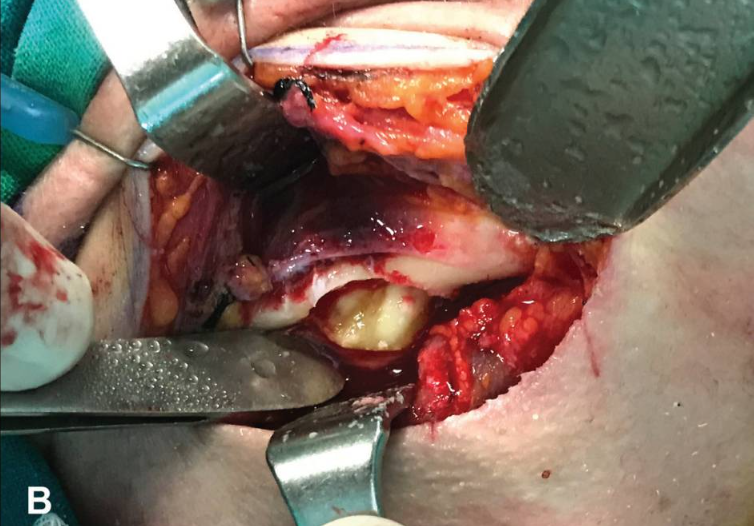

由于临床症状提示存在炎症,决定连同囊性病变一起拔除阻生牙。在首次开具抗生素以缓解炎症症状后,患者接受了手术。选择了全身麻醉下的口外入路作为首选手术方式。在仔细准备手术部位后(见图1B),在右下颌下缘以下约2厘米处进行颌下皮肤切口,并切开颈阔肌。面神经下颌边缘支(VII)在颈深筋膜的浅层立即被识别,并在结扎面静脉和动脉后从手术区域退回。随后切开翼内肌腱索,接着切开覆盖右下颌下缘的骨膜。

通过小心翻起骨膜,从下颌骨下方到达阻生部位(见图2A)。使用低速手机及无菌生理盐水进行骨切开,暴露出阻生牙(见图2B)。立即取出阻生的第三磨牙及其囊性病变(见图3A)。手术过程中未暴露下牙槽神经。手术创口经过彻底的抗菌剂和生理盐水冲洗后,放置引流管并逐层闭合软组织。

B) 在切除覆盖阻生部位的颊骨板后,暴露出阻生的第三磨牙及囊肿。